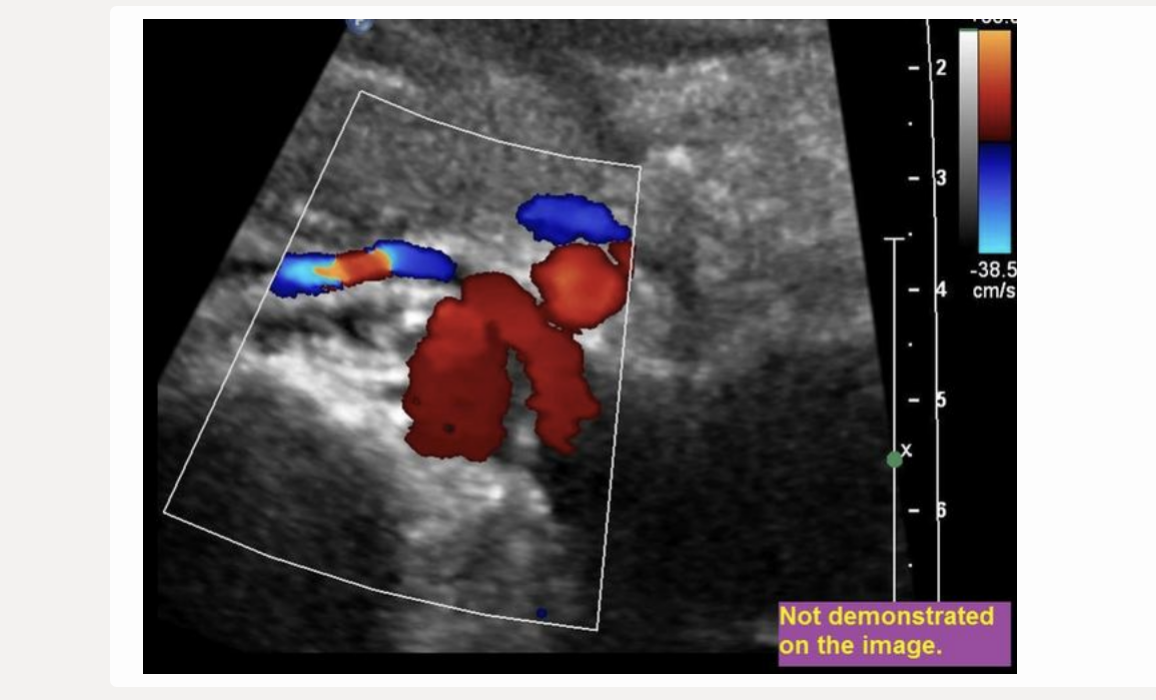

![<p>find the left renal vein</p><p>.</p><p>[left renal vein = between SMA + AO]</p>](https://knowt-user-attachments.s3.amazonaws.com/522e32e3-0c34-4507-81e5-c8f625b0171c.png)

find the left renal vein

[left renal vein = between SMA + AO]

left renal vein = between SMA + AO